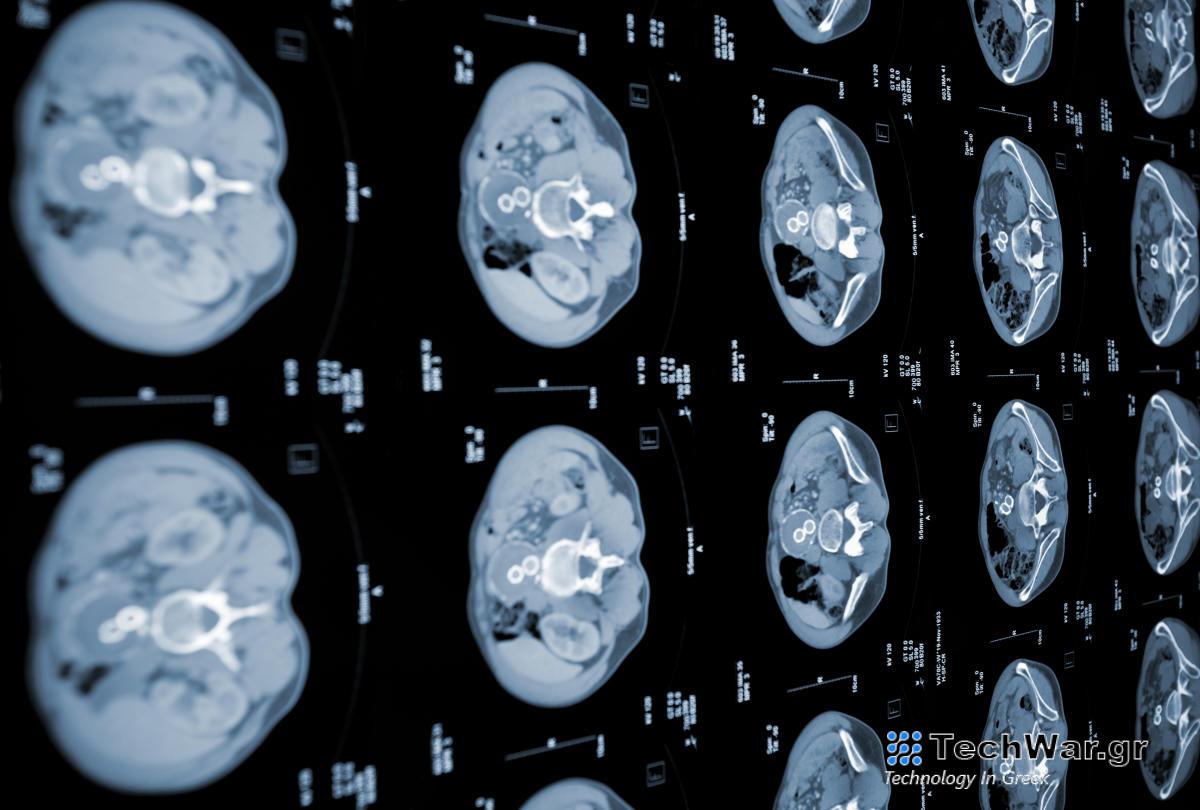

Οι ειδικοί του MIT αναπτύσσουν μοντέλα AI που μπορούν να ανιχνεύσουν έγκαιρα τον καρκίνο του παγκρέατος

ούργησε δύο αλγόριθμους μηχανικής μάθησης που μπορούν να ανιχνεύσουν τον καρκίνο του παγκρέατος σε υψηλότερο όριο από τα τρέχοντα διαγνωστικά πρότυπα. Τα δύο μοντέλα μαζί σχηματίστηκαν για να δημιουργήσουν το νευρωνικό δίκτυο «PRISM». Έχει σχεδιαστεί για να ανιχνεύει ειδικά το αδενοκαρκίνωμα του παγκρεατικού πόρου (PDAC), την πιο διαδεδομένη μορφή καρκίνου του παγκρέατος.

Τα τρέχοντα τυπικά κριτήρια προσυμπτωματικού ελέγχου PDAC πιάνουν περίπου το 10 τοις εκατό των περιπτώσεων σε ασθενείς που εξετάζονται από επαγγελματίες. Συγκριτικά, το PRISM του MIT ήταν σε θέση να αναγνωρίσει περιπτώσεις PDAC στο 35 τοις εκατό του χρόνου.

Αν και η χρήση δεν είναι ένα εντελώς νέο επίτευγμα, το PRISM του MIT ξεχωρίζει λόγω του τρόπου με τον οποίο αναπτύχθηκε. Το νευρωνικό δίκτυο προγραμματίστηκε με βάση την πρόσβαση σε διάφορα σύνολα πραγματικών ηλεκτρονικών αρχείων υγείας από ιδρύματα υγείας σε όλες τις ΗΠΑ. Τροφοδοτήθηκε με δεδομένα από περισσότερα από 5 εκατομμύρια ηλεκτρονικά αρχεία υγείας ασθενών, τα οποία οι ερευνητές από την ομάδα είπαν ότι «ξεπέρασαν την κλίμακα» των πληροφοριών που τροφοδοτήθηκαν σε ένα μοντέλο τεχνητής νοημοσύνης σε αυτόν τον συγκεκριμένο τομέα έρευνας. “Το μοντέλο χρησιμοποιεί κλινικά και εργαστηριακά δεδομένα ρουτίνας για να κάνει τις προβλέψεις του και η ποικιλομορφία του πληθυσμού των ΗΠΑ είναι μια σημαντική πρόοδος σε σχέση με άλλα μοντέλα PDAC, τα οποία συνήθως περιορίζονται σε συγκεκριμένες γεωγραφικές περιοχές όπως μερικά κέντρα υγειονομικής περίθαλψης στις ΗΠΑ,” Kai Jia , είπε ο ανώτερος συγγραφέας της

Το AI λειτουργεί αναλύοντας δημογραφικά στοιχεία ασθενών, προηγούμενες διαγνώσεις, τρέχοντα και προηγούμενα φάρμακα σε σχέδια φροντίδας και εργαστηριακά

. Συλλογικά, το μοντέλο λειτουργεί για να προβλέψει την πιθανότητα καρκίνου αναλύοντας δεδομένα ηλεκτρονικών αρχείων υγείας σε συνδυασμό με πράγματα όπως η ηλικία του ασθενούς και ορισμένοι παράγοντες κινδύνου που είναι εμφανείς στον τρόπο ζωής του. Ωστόσο, το PRISM εξακολουθεί να είναι σε θέση να βοηθήσει στη διάγνωση τόσο πολλών ασθενών με τον ρυθμό που η τεχνητή νοημοσύνη μπορεί να φτάσει στις μάζες. Προς το παρόν, η τεχνολογία δεσμεύεται και επιλέγει ασθενείς στις ΗΠΑ. Η υλικοτεχνική πρόκληση της κλιμάκωσης της τεχνητής νοημοσύνης θα περιλαμβάνει την τροφοδοσία του αλγόριθμου με περισσότερα διαφορετικά σύνολα δεδομένων και ίσως ακόμη και παγκόσμια προφίλ υγείας για την αύξηση της προσβασιμότητας.